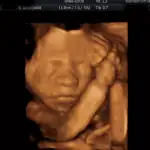

3D/4D ultrazvuk

Tyto fotografie jsou pořízené přístrojem Voluson 730